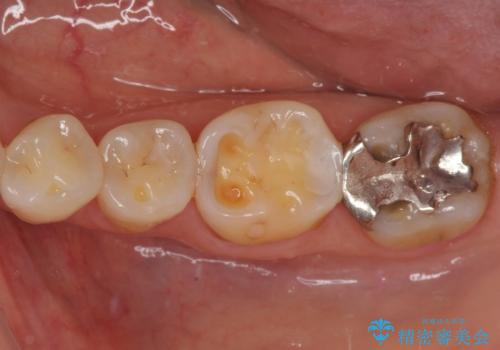

奥歯の銀歯をゴールドでしっかりと治療

- 奥歯の銀歯をすべてゴールドにすることを希望された患者様です。

セラミックインレーによる補綴治療も提案しましたが、ご自身で強い咬合力を認識しており、歯にもインレーにもダメージの少ないゴールドインレーにて処置することとしました。